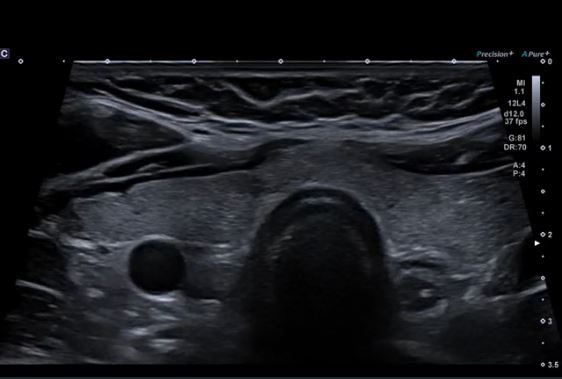

Однорідність структури щитовидної залози демонструється за допомогою лінійного датчика PLU-805BT.